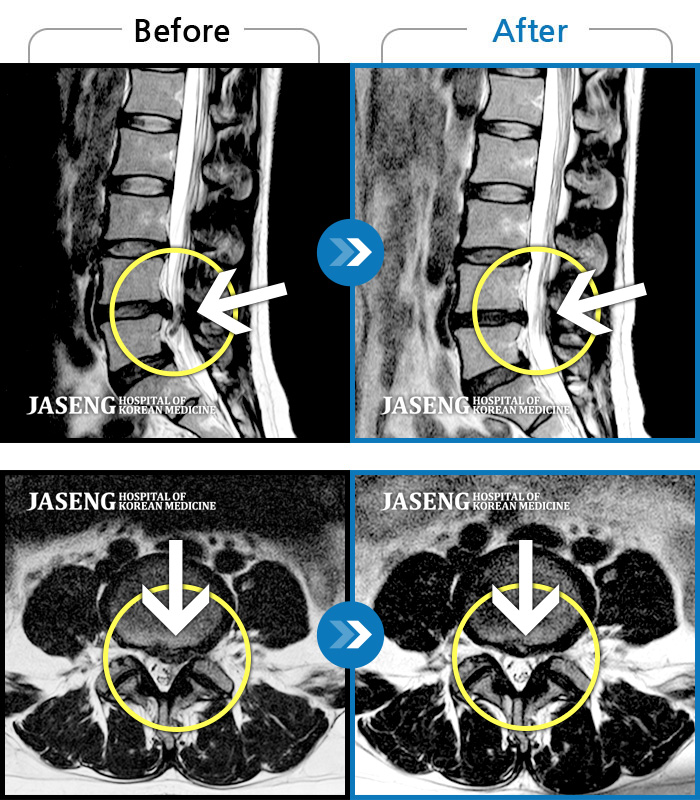

Before

After

환자에게 사전 동의를 받아 동일 조건에서 촬영되었습니다.

개인에 따라 치료 후 부작용이 발생할 수 있으니 의료진과 상담 후 치료를 진행하시기 바랍니다.

화장실 청소를 한 후 좌측 골반통증 및 좌측 엄지발가락 얼얼함, 근력저하가 있었다.

우측 허리 뻐근한 통증, 우측 허벅지부터 발목까지 이어지는 당김